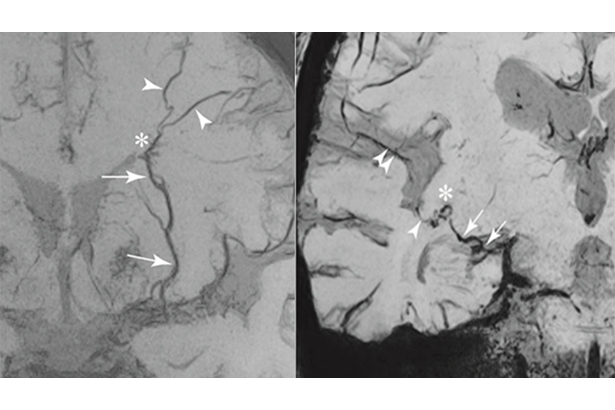

飛速3D成像(FAST 3D)技術可用于頭顱血管斑塊成像,僅需3分鐘,實現高分辨顱內血管壁成像。圖像信噪比高,掃描時間短。